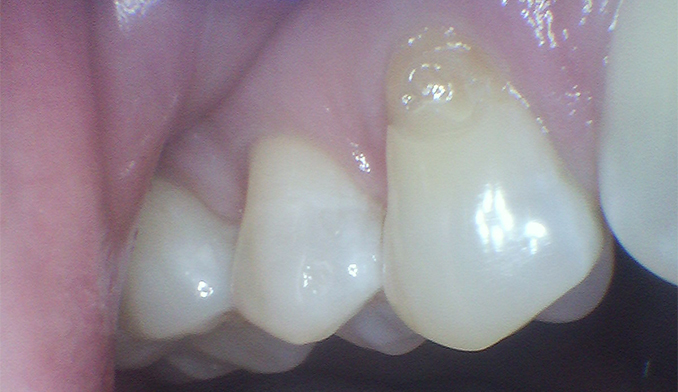

Gumline Bonding for Esthetics and Protection

The patient requested bonding along the gumline to improve appearance and protect exposed areas. We placed tooth-colored fillings to restore a smooth, natural look and enhance long-term oral health.